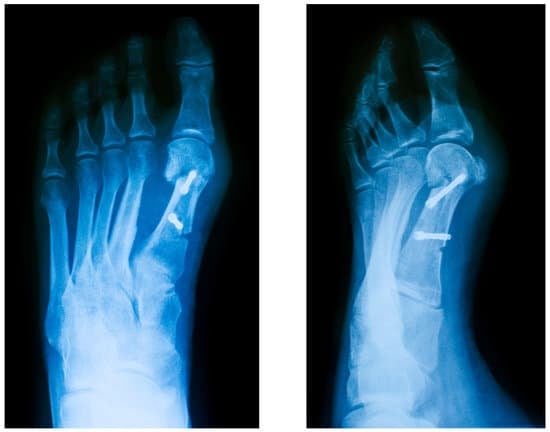

수술 절차

무지외반증 수술 절차는 다음과 같습니다\

마취: 전신 마취 또는 국소 마취를 시행합니다.

절개: 변형된 부위에 절개를 가합니다.

변형 교정: 선택된 수술 방법에 따라 변형된 뼈와 연부 조직을 교정합니다.

고정: 나사, 핀, 판 등을 사용하여 뼈를 고정합니다.

봉합: 절개 부위를 봉합합니다.